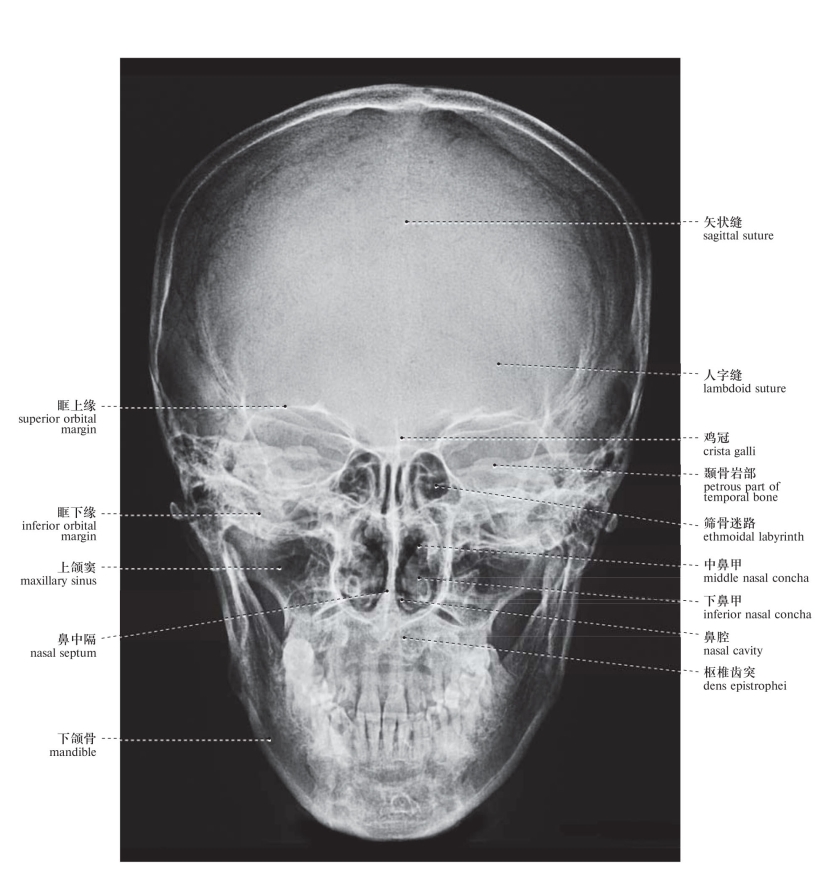

图46 颅X线像(前后位)

Radiograph of the skull (anteroposterior view)